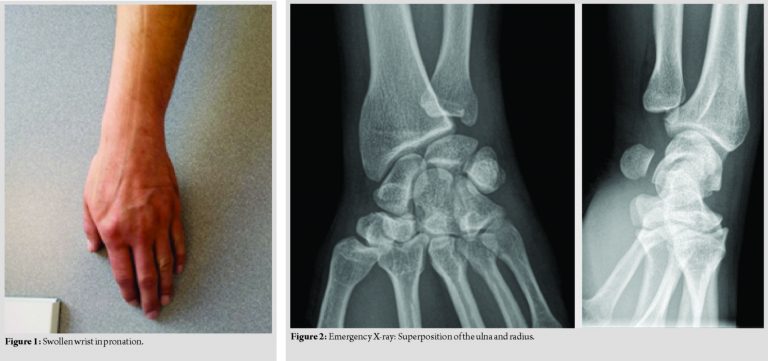

A 36-year-old man, right-handed, manual worker, without medical background or hyperlaxity presented himself to the emergency room after an injury of the upper right limb. The patient was a sportsman, martial arts competitor. Trauma was related to an accident on the public road (electric scooter). Fall was described as wrist in pronation and hyperextension. On arrival, the patient reported a severe localized pain in the DRUJ. Wrist was in pronation (Fig. 1).

Mobility in flexion-extension was preserved. Pronation and supination were blocked and painful. The patient did not have a neurovascular deficit. Edema helped diagnosis. The ulnar head, palpable, was prominent in volar side. Diagnosis was supposed on the AP wrist and lateral views (Fig. 2) and confirmed with a computed tomography (CT)scan (Fig. 3). A radiological series including forearm and elbow X-rays confirmed the isolated character of the lesion. The patient was managed in the operating room under general anesthesia. Reduction by a closed manipulation was performed. In forced pronation, the operator maintained volar pressure on the ulnar head. The reduction was confirmed by the perception of a jerk. Post-reductionX-rays(AP, lateral, and dynamic pronosupination) made at the operating room confirmed the reduction. The test was performed in full flexion-extension and full pronation-supination. The perfectly stable aspect of the DRUJ made it possible to allow a non-operative management and avoid temporary stabilization with K-wire(Fig. 4).